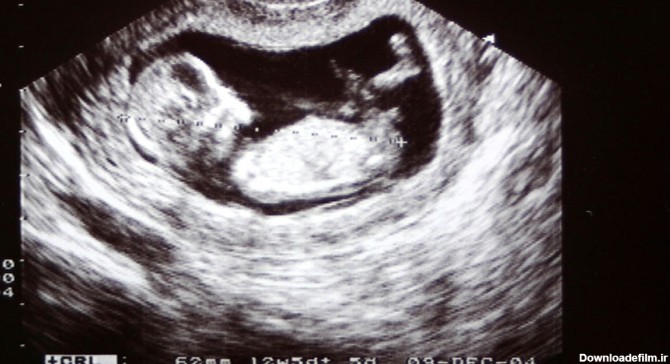

سونوگرافی جنین یا سونوگرافی حاملگی یک روش تصویربرداری است که از امواج صوتی برای ایجاد تصاویری از وضعیت و نحوه رشد جنین در رحم استفاده میکند.

سونوگرافی تشخیص جنسیت(جنین پسر است یا دختر)؛ اواخر سه ماهه دوم بر اساس تجسم دستگاه تناسلی و اواخر سه ماهه اول و اوایل سه ماهه دوم بر اساس جهت اندام تناسلی است.